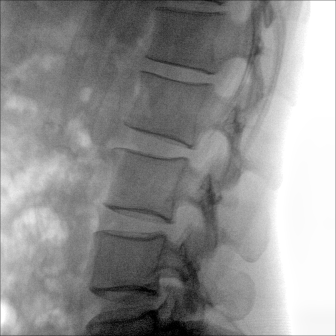

大尺寸動(dòng)態(tài)平板探測(cè)器,高DQE、低噪聲、圖像清晰。采用多分辨率圖像增強(qiáng)處理技術(shù),不同部位不同圖像處理算法,滿足客戶多樣化的需求。